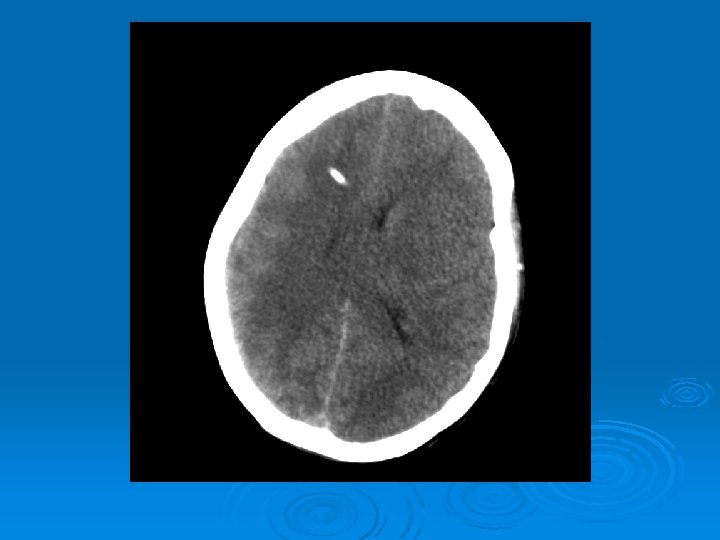

Course: Ø 3 PM, RN noticed anisocoria and L pupil non-reactive. Ø Neurology STAT dose mannitol and w/ dilantin. Ø Pt went for stat head Ct:

CT head 2/11/07 Ø A right frontal ventriculostomy catheter Ø Diffuse sulcal effacement with thickening of the cortex. Ø Loss of gray-white differentiation and hypodensity in the left parietooccipital region. Ø There is diffuse hypodensity of the cerebellum and brainstem. Ø Ø Ø The basilar cisterns are nearly completely effaced. Ø Impression: Ø Worsened diffuse cerebral edema The lateral ventricles are smaller

Course: Ø Neurosurgery saw pt: on exam she had lost cough, gag reflexes, corneal reflexes, she had flexed RUE, semipurposeful with bilateral extended LE. Ø Concern for herniation: placed Ø ICP 35 -40 10 th-11 th EVD